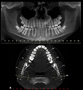

Radiografia Panorâmica